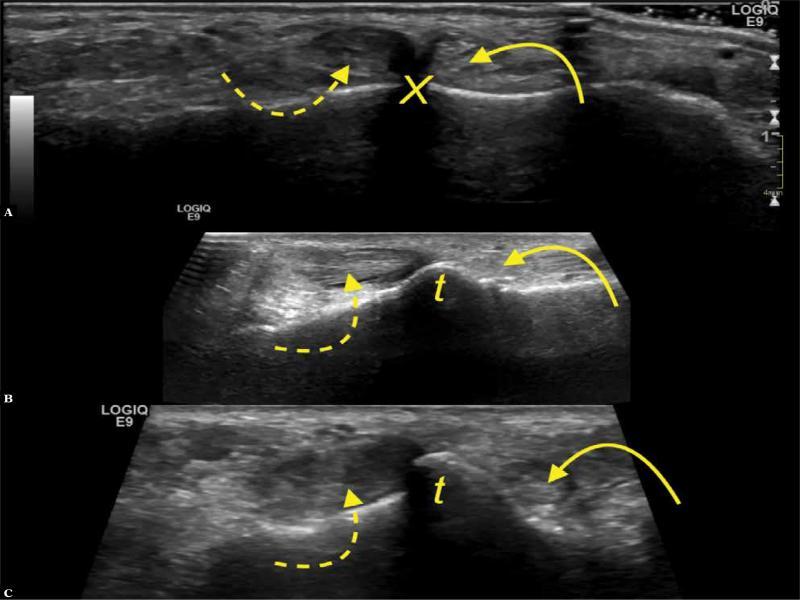

The SPR was found to be connected to at least one of the examined lateral structures in 16 cases (25.3%) on US, and in 14 cases (22.2%) on MR, whereas no connections at all were identified in 6 cases (9.5%) on MR and 3 cases (4.8%) on US; the differences are not statistically significant (p >0.05). When the SPR did not extend beyond the outer outline of the lateral malleolus, connections were considered absent (Fig. 1). The SPR connections are shown in Tab. 1 and other anatomical variations in Tab. 2.

Fig. 1.

A 19-year-old patient with a clinical suspicion of rheumatoid arthritis. A. ultrasound, transverse section. B, C. proton density-weighted transverse sections. Fib – fibula. SPR – curved arrow. No connection with IER is present